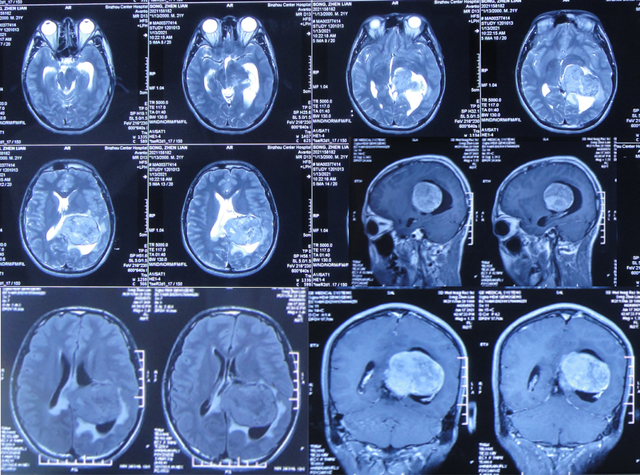

继续抗感染治疗1周的时间,仍精神差,食欲差,间断发热,期间3次查头颅影像(2021年1月29日头颅核磁增强(图-10)、2021年1月31日头颅CT(图-11)、2021年2月3日头颅核磁增强(图-12)均示颞角逐渐有扩张,有感染。

图-10:2021年1月29日头颅核磁增强

图-11:2021年1月31日头颅CT

图-12:2021年2月3日头颅核磁增强

2021年2月5日(脑膜瘤切除术后颅内感染3周)住入李小勇脑脊液科,入院时:精神差,食欲差,体温高(图-13);查头颅CT示脑瘤术后状态(图-14);(外院)2021年2月3日头颅核磁示有脑脓肿(图-12)。

图-13:2021年2月5日入院时

图-14:2021年2月5日头颅CT

入院后3天即2021年2月8日,左颞角脑室腹壁外引流术(图-15)。

图-15:2021年2月8日头颅CT

左颞角脑室腹壁外引流术后8天即2021年2月16日,查头颅CT示颞角缩小(图-16)。

图-16:2021年2月16日头颅CT

左颞角脑室腹壁外引流术后21天即2021年3月1日,查头颅CT示颞角仍有扩张(图-17)。

图-17:2021年3月1日头颅CT

左颞角脑室腹壁外引流术后23天即2021年3月3日,头颅CT增强和核磁增强示有脑脓肿(图-18、图-19)。

图-18:2021年3月3日头颅CT增强

图-19:2021年3月3日头颅核磁增强